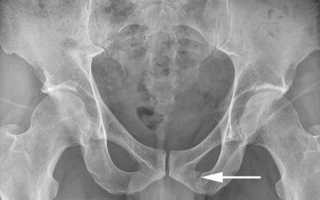

- перелом без смещения. В области совокупности костных элементов таза (кольца) конструктивная целостность сохраняется,

Внимание! В большинстве случаев переломы лонных костей не приводят к нарушению общей тазовой конструкции.

При переломах лонной кости без смещения и изменения состояния тазового кольца, срастание обломков осуществляется благодаря иммобилизации и не требует хирургического вмешательства. Кроме того, производится прием следующих медикаментов: